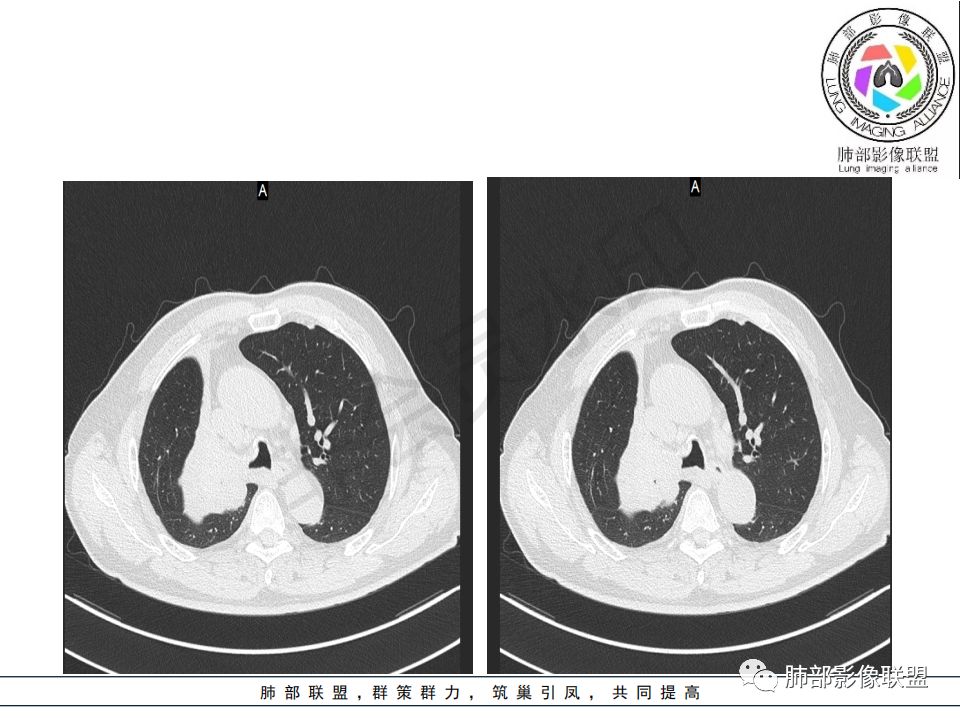

病史:男.77岁,咳嗽1月;干咳,少许白痰,无发热,2013胃癌术后,角蛋白24.65(0-3.07),SCC和proGRP不高;

影像:影像右侧大支气管阻塞,临床没有症状或很轻微,要想到胃腺癌转移;胸壁代偿好,透亮度稍低不明显,慢性过程;34.8-52.5HU,主病灶支气管前壁另有1结节,都做成增强两期了,动脉期较平扫有强化;

诊断:多发,转移,无淋巴结及胸腔积液;

鉴别:原发鳞癌。

病理结果:腺癌,考虑来源消化道

1.右肺上叶较大块影,密度不均,轻度强化并见低密度区,所属支气管截断并腔内突入,是符合肺鳞癌的影像学特征和生物学行为的。

2.胃癌常会首先胃旁淋巴结、腹主动脉淋巴结转移,肝脏血行转移,以及双肺多发转移,本例孤立右肺上叶病灶巨大,多有不符。

3.胃癌多血供,患者肺内病灶轻度强化。